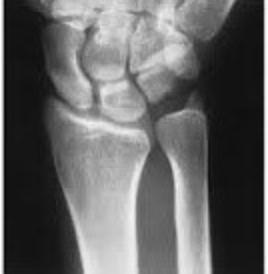

遠端橈骨骨折是最常見的骨折類型之一,約佔所有骨折的十分之一。多發生於跌倒時,手腕本能撐地所承受的衝擊,導致骨折並出現「銀叉變形」(Silver Fork Deformity)。這類骨折是骨科醫師日常最常遇到的狀況之一。

臺北市立聯合醫院陽明院區骨科主任高鈞彥表示,有高達六至八成的患者,骨折同時會伴隨軟組織傷害,如肌腱斷裂、神經損傷、三角纖維軟骨(TFCC)損傷或腕骨韌帶受損。所幸有超過九成的軟組織傷害可自癒,只要治療得宜,大多有良好結果。